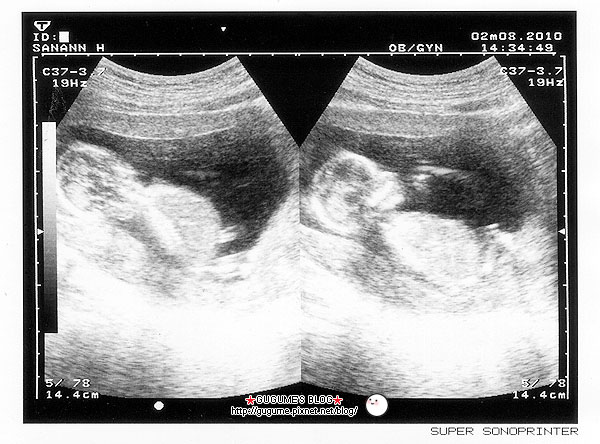

2/8星期一去做了第二次產檢

一照超音波

連醫生都說長大很多呢

而且寶寶雖然不像上次一樣跳彈簧床

不過他有在翻身呢

本來是側面

還轉正面手舉起跟我打招呼咧

至於性別

醫生說還看不太清楚

要等下次去才會知道